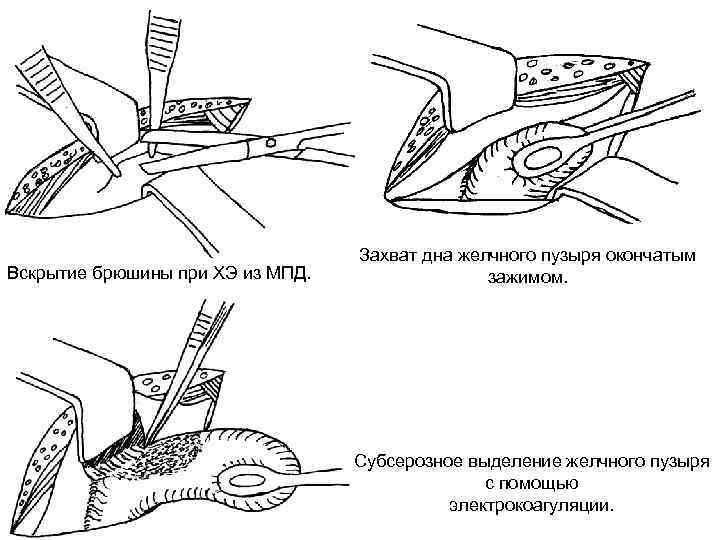

Кіші жолмен жасалатын холецистоэктомия Көрсеткіштері: - жедел калькулезді холецистит - холецистолитиаз, холедохолитиаз, кеңеймеген; -ЛХЭ кезіндегі техникалық қиыншылықтар. Қарсы көрсеткіштер: - іш қуысы ағзаларын интраоперационды ревизия жасау қажеттілігі; - Жайылған перитонит.

Вскрытие брюшины при ХЭ из МПД. Захват дна желчного пузыря окончатым зажимом. Субсерозное выделение желчного пузыря с помощью электрокоагуляции.

Инверсия выделенного на 2/3 желчного пузыря. Схемы дренирования после ХЭ из МПД